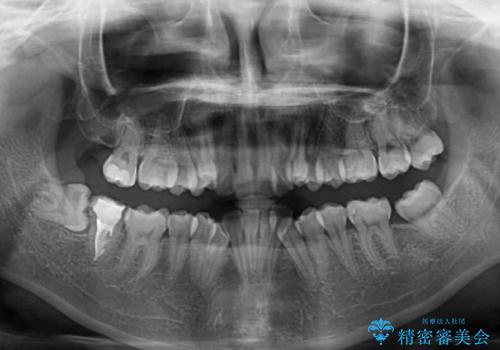

上下の八重歯とクロスバイト ワイヤー装置での抜歯矯正

- 八重歯とクロスバイトを気にして来院された患者様です。

上下ともに八重歯が顕著であり、前歯のクロスバイトがあったため、上下左右の第一小臼歯4本を抜歯し、ワイヤー装置での抜歯矯正を行うこととしました。